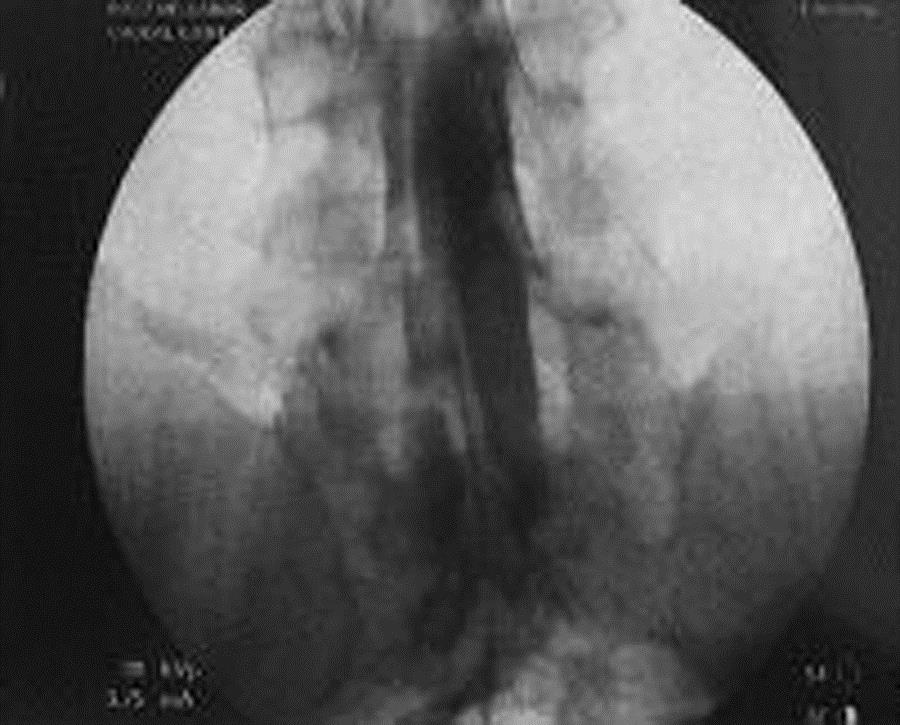

A catheter is inserted in the caudal epidural space and steered up to the area of scarring. This is done in our fluoroscopy suites under sterile conditions with IV sedation.

- X-ray contrast (Nonionic DYE) so that the scarred space can be clearly visualized